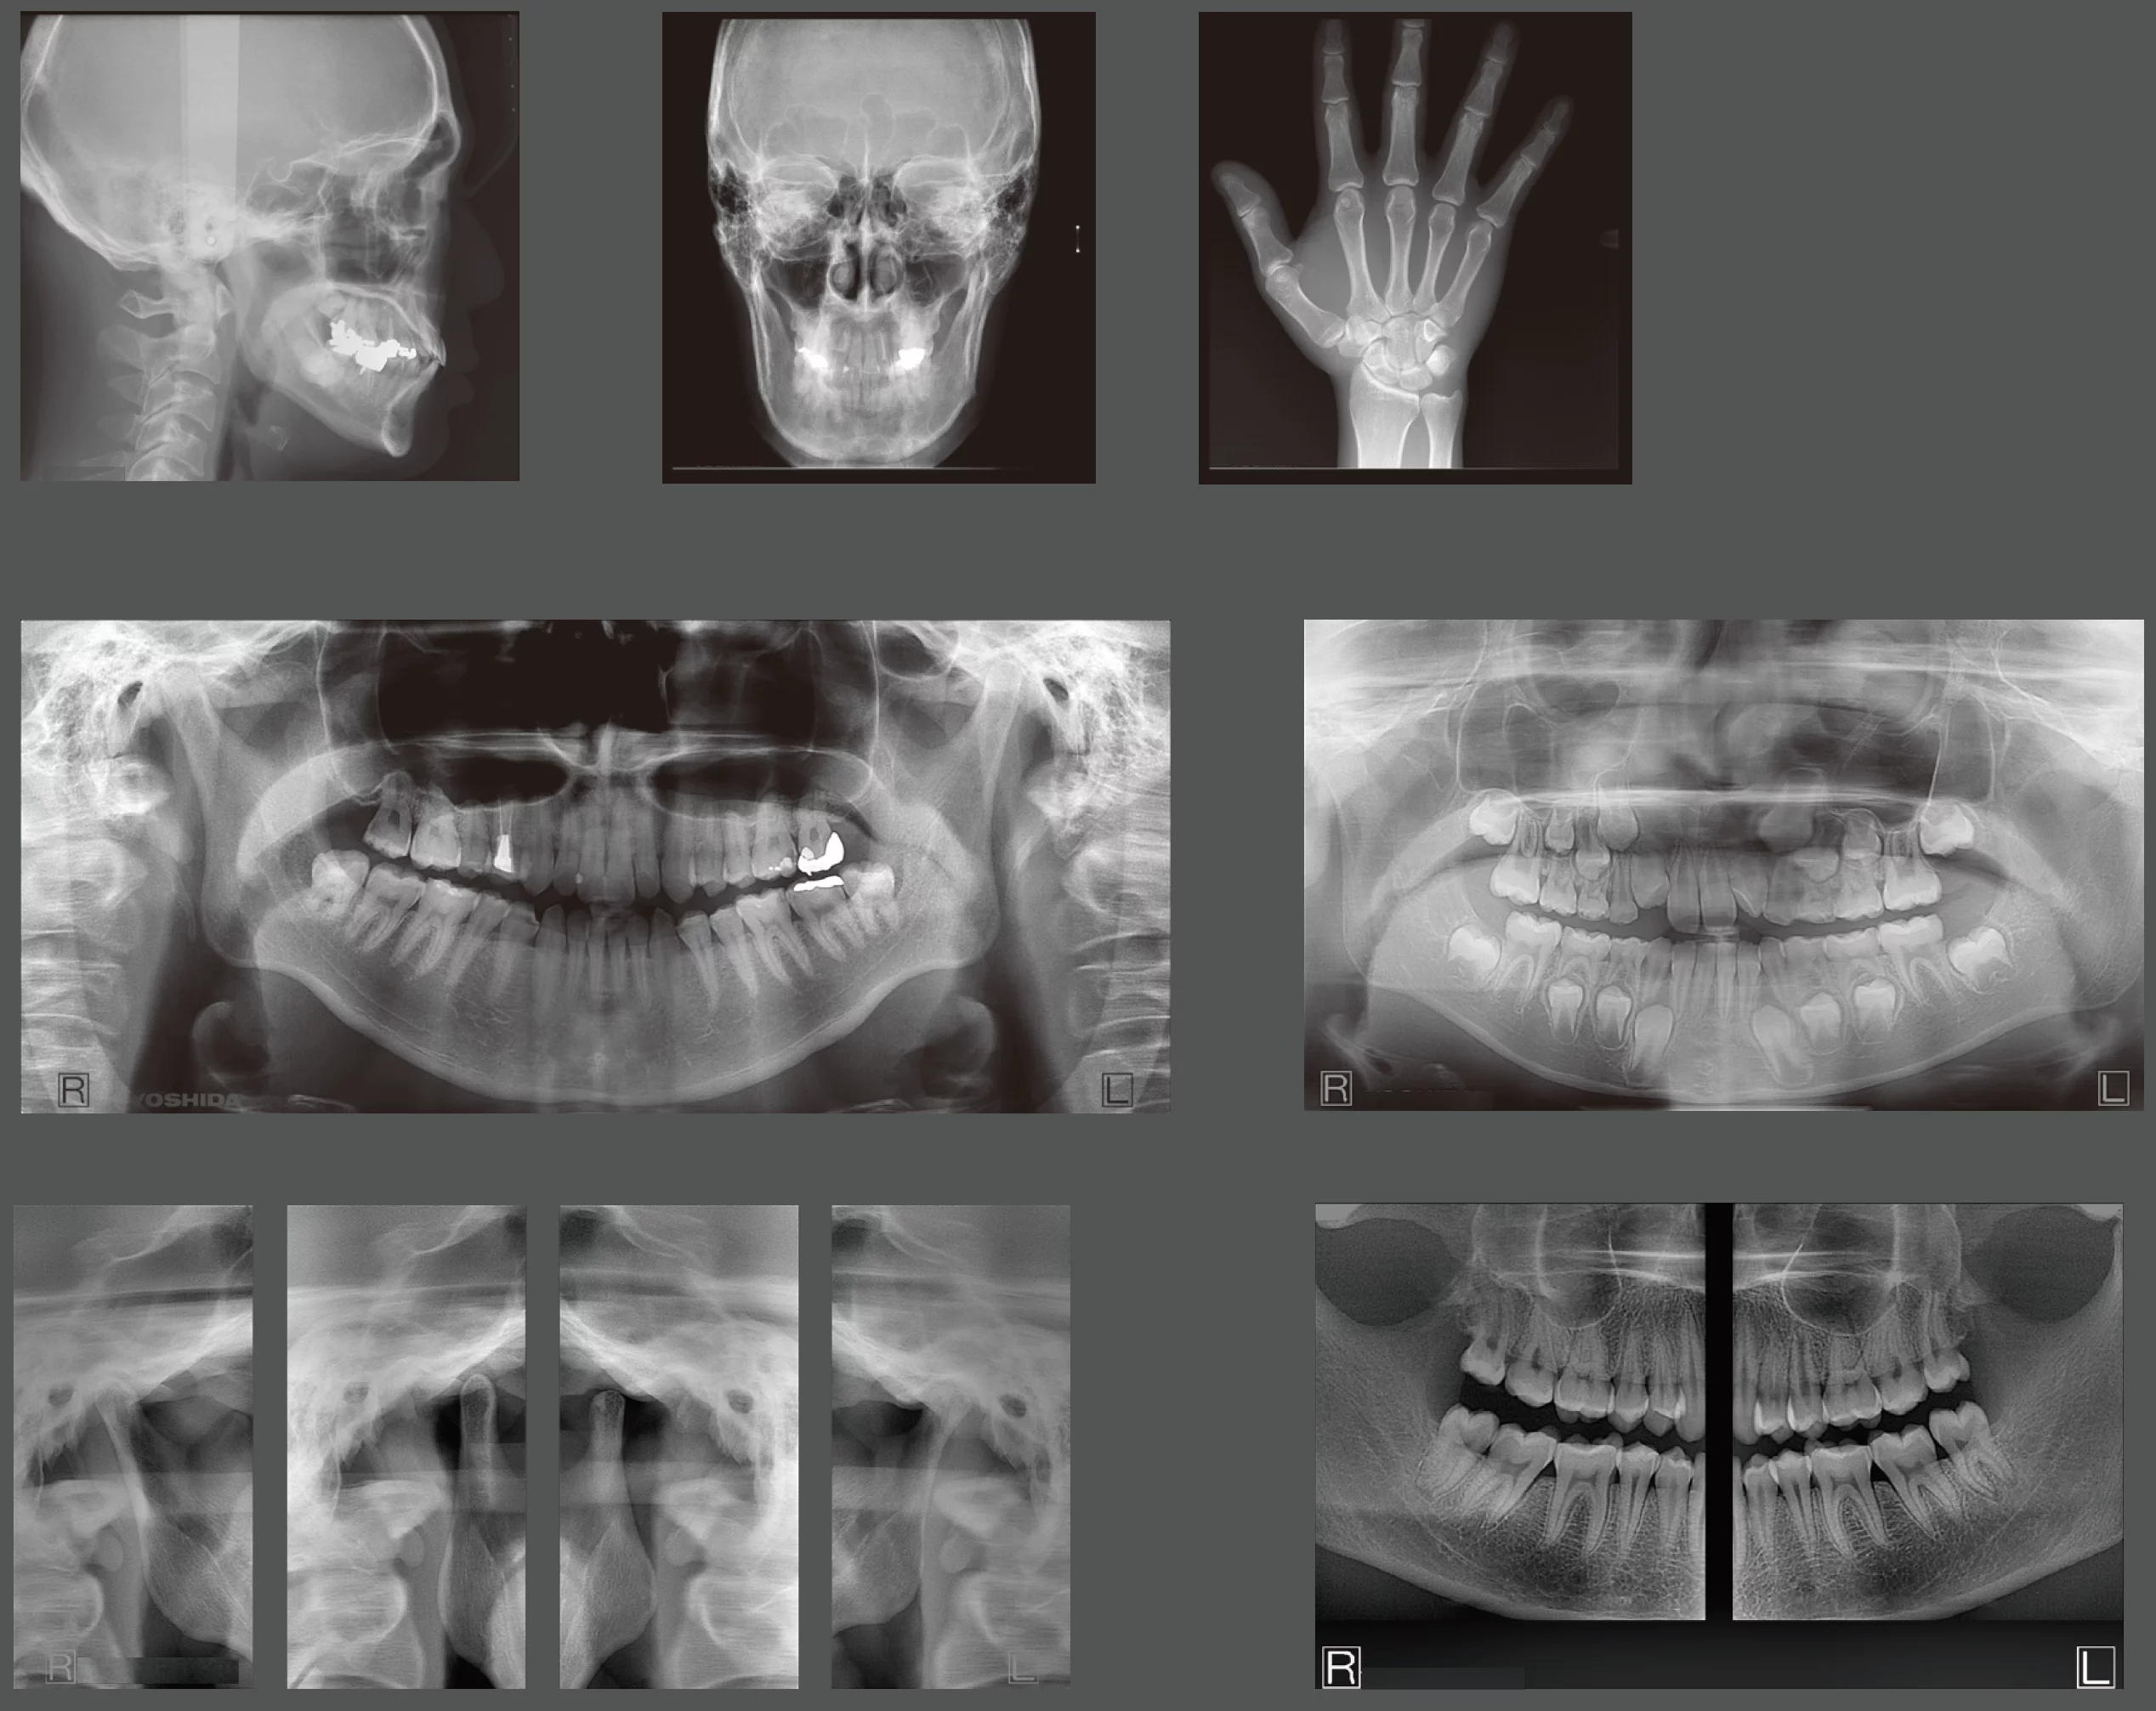

For dental professionals that need both 3D volumes AND 2D panoramic radiographs to be high resolution.

Most dental cone beam systems use the same sensor for 2D panoramic radiographs as they use for the 3D scans. This means that one (or both) modality is typically suboptimal.

A Panoramic X-Ray to be proud of

Most of our dental professionals depend on their cone beam system to produce a high-quality panoramic x-ray in addition to a high-quality 3D volume. Most dental cone beam systems sacrifice the performance of their panoramic modality by attempting to use the 3D sensor to perform 2D panos. The X-era uses a cone beam sensor for cone beam scans, and a panoramic sensor for panoramic scans.

In fact, the panoramic sensor is the same high-quality sensor that we use in our wildly successful pan-only platform, the Panoura 18S. Here’s what makes the panoramic modality so powerful…